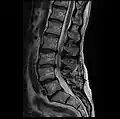

MRI lumbar spine post-hemilaminectomy (sagittal T2 FRFSE)

-

MRI lumbar spine post-hemilaminectomy (sagittal T1 FSE)